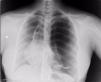

Mujer de 31 años de edad, natural de Pakistán, sin antecedentes médico-quirúrgicos de interés, que consulta por dolor pleurítico de 2 días de duración en el hemitórax izquierdo, irradiado a flanco ipsilateral con hemoptisis leve. A su llegada a urgencias, se objetiva fiebre de 38°C y escalofríos. A la auscultación, destaca hipofonesis izquierda, por lo que se realiza una radiografía de tórax (fig. 1; véase el comentario de la imagen).

Radiografía simple de tórax posteroanterior. Desplazamiento mediastínico que incluye la silueta cardiaca hacia la derecha, con pérdida de trama broncovascular en el campo pulmonar izquierdo sugestivo de gran bulla y neumotórax apical izquierdo. Imágenes quísticas basales izquierdas con nivel hidroaéreo.